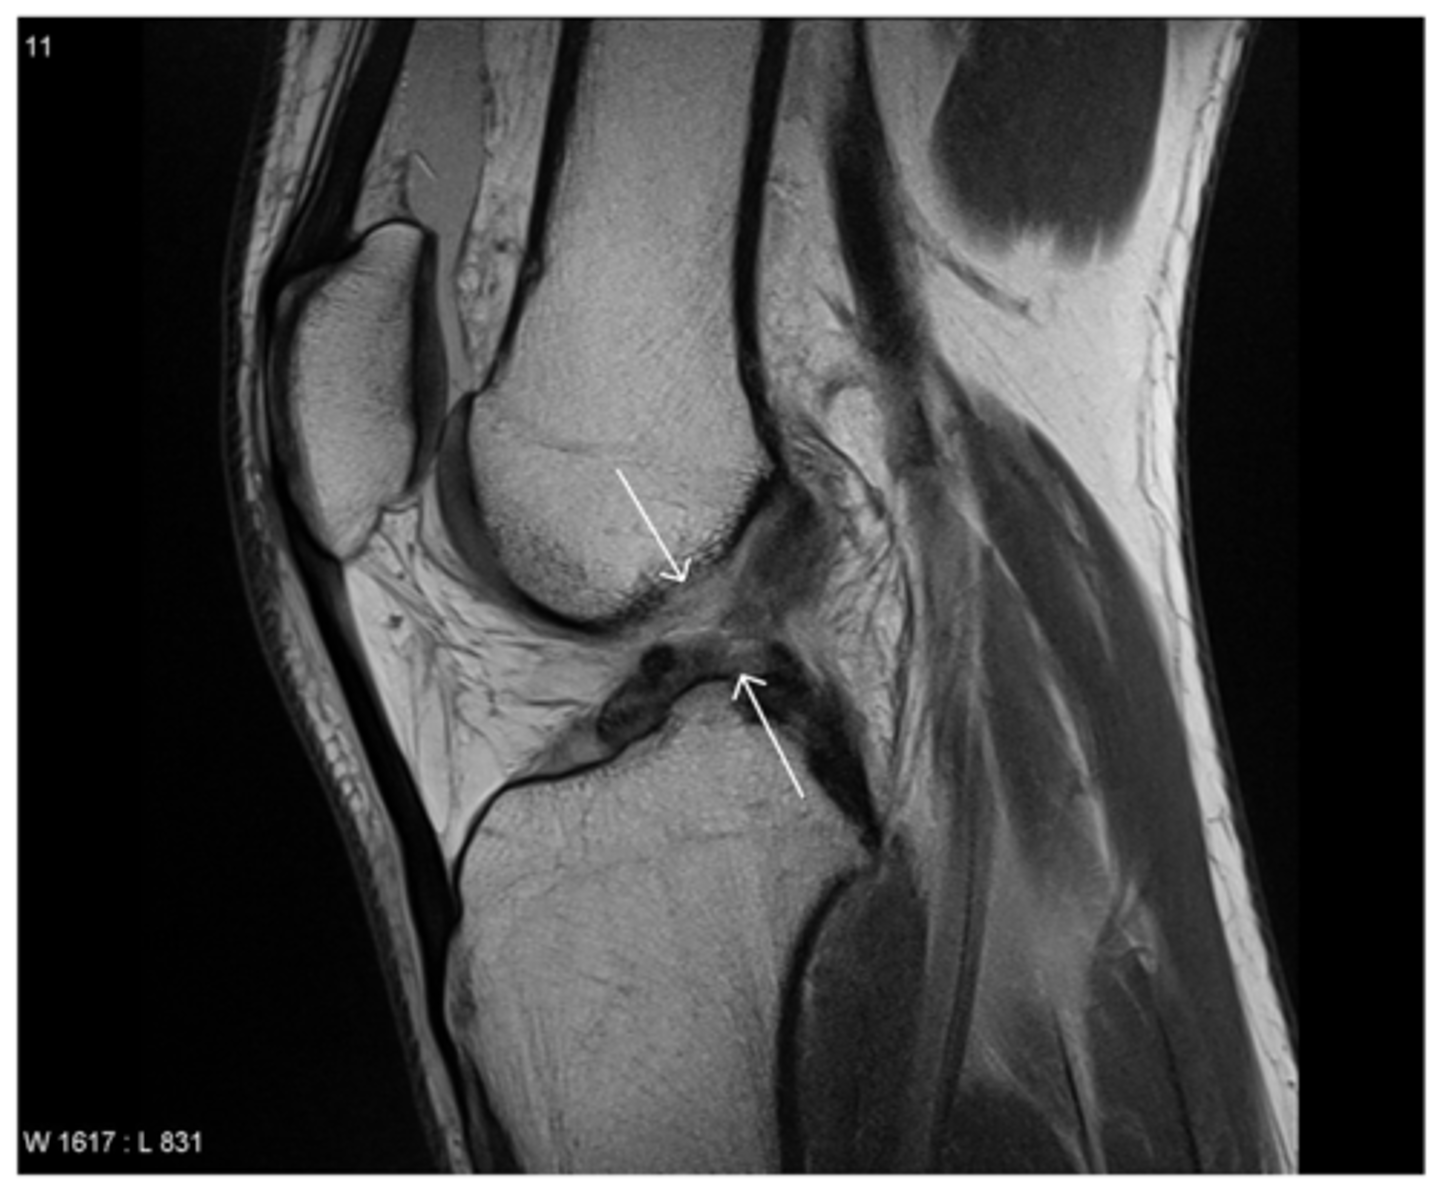

Tear of the PCL -- normally, ligaments are pulled taut and appear straight; if they are torn, they appear wavy and/or curved over

Define the pathology. How do you know?

Tear of the PCL -- when ligaments curve like this and/or get wavey, it is a dead give-a-way that a tear is present

Define the pathology.